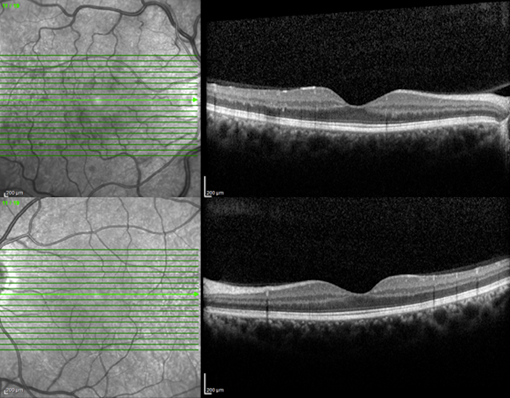

A 35-year-old, male, Caucasian patient presented to our clinic with complain of blurred vision in his right eye. Unilateral blurred and low vision has persisted for 6-month and the patient had been underwent an intravitrealinjection in the clinic. The patient was underwent a detailed ophthalmological examination. The best corrected visual acuity (BCVA) was found as 20/32 in the right eye and 20/20 in the left eye with Snellen chart. Intraocular pressure was bilateral 15mmHg with Goldmann applanation tonometer. In biomicroscopic examinations was completely normal for two eyes. After dilation, retinal arterial narrowing, arteriovenous nipping, retinal hemorrhages, roth spots, and loss of foveal light reflex were seen in the right fundus while the left fundus was completely normal (Figure 1). In optical coherence tomography (OCT), diffuse macular thickening in the right eye and normal macular configuration in the left eye were seen Figure 2. Fundus fluorescein angiography (FFA) was performed and delay in arterial filling, capillary drop-out, and foveal late-phase leakage were present in the right eye although left eye was normal (Figure 3). We looked for an anterior and posterior segment neovascularization using 3-mirror lens and we planned to closely follow-up for the patient because of there was no any neovascularization in clinical examination and suspicious leakage in previous FFA.

Figure 2 Optical coherence tomography images of the patient.